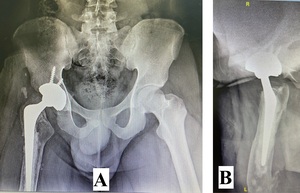

A 22-year-old man presented to our hospital in December 2020 following a motor vehicle accident. The patient had no significant medical, family, or allergy history. He worked in a metal factory and occasionally smoked. The sustained injuries included a closed fracture of the right neck of the femur, an open right supracondylar femur fracture (Gustilo 3C), and an open midshaft fracture of the right tibia (Gustilo 2) (Figures 1, 2, and 3).

Initial management involved screw fixation of the femoral neck, wound debridement of the right thigh, and placement of an external fixator across the right knee (Figures 4 and 5), followed by a one-week course of intravenous cefuroxime. By January 2021, the right leg had become gangrenous and deemed nonviable. Right above-knee amputation (AKA) with adductor myodesis was performed, followed by intravenous cefuroxime for another week.